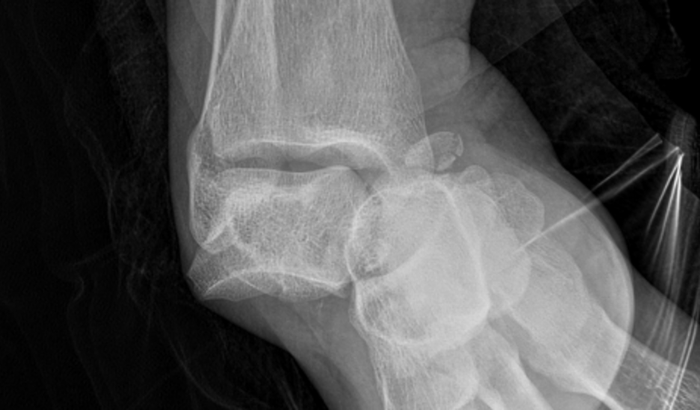

Estava em sala de aula expondo e organizando a sala com as atividades desenvolvidas por eles, subi em uma escada para pendurar no teto as atividades dos pequeninos e a escada deslizou e soltou a trava, prendendo um dos pés na escada, ao soltar o pé, cai no chão e sofri uma luxação no tornozelo direito, diversas fraturas, maleolo medial, 4 metatarso, e na tíbia. Houve ruptura dos ligamentos e preciso realizar cirurgia ortopédica com urgência.

Cirurgia para reconstruir os ligamentos, fazer um implante e remover um osso quebrado que está dentro do pé solto.